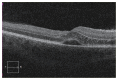

Purpose: To describe the clinical presentation, ocular complications, treatment, and visual outcomes in a series of 17 patients from New Zealand with neuroretinitis secondary to Bartonella henselae.

Results: Seventeen patients (19 eyes) were included with 11 (65%) being female. The mean age at presentation was 28.3 ± 12.3 years (range, 13-60 years). The mean presenting visual acuity (Early Treatment Diabetic Retinopathy Study testing) was 50 ± 23 (range, 4-90). The mean final visual acuity was 78 ± 12 (range, 45-90). Eleven patients (65%) had cats or kittens at home, with only one (6%) recounting a history of being scratched. Eight patients (47%) demonstrated the characteristic macular star at presentation, with all eventually developing macular star within a mean of 6 days. Four patients (24%) had macular oedema, three (18%) had vasculitis, two (12%) had uveitis, two (12%) had disc granuloma, and one (6%) had multifocal chorioretinitis. Six patients (35%) were treated with rifampicin and doxycycline, one (6%) with rifampicin and azithromycin, two (12%) with doxycycline only, two (12%) with co-trimoxazole monotherapy, and one patient (6%), who was breast-feeding, was treated with erythromycin. Four patients (24%) did not have receive any treatment.

Conclusions: The characteristic macular star is not always manifest at initial presentation for patients with neuroretinitis secondary to B. henselae, nor is there always a preceding history of cat exposure. Not all patients require treatment to have a good visual outcome, and the immune status of the patient is important.